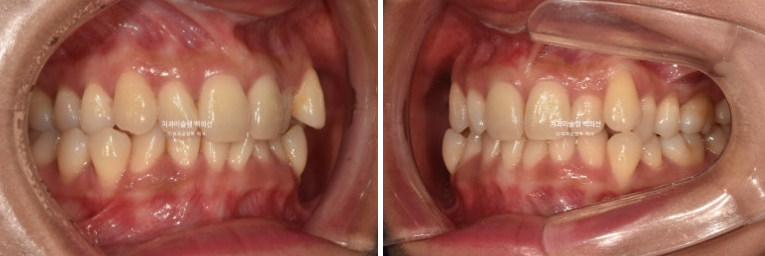

1년 전, 교정치료를 위해 온 환자분입니다.

24.08

환자분이 고치고 싶은 것은 덧니입니다.

송곳니와 작은어금니 덧니가 보이며 작은어금니가 거꾸로 물리는 반대교합도 보입니다.

앞니 중심선은 약 2mm 어긋나 있습니다.

위 앞니가 아래앞니를 많이 덮어 깊게 물리는 과개교합도 있습니다.

덧니로 배열에서 튀어나와있는 치아들은 잇몸이 내려가 있습니다.

다행히 큰어금니 교합은 좋은 편

24.08~25.08

옥니였던 앞니 각도가 정상각도를 찾았습니다.